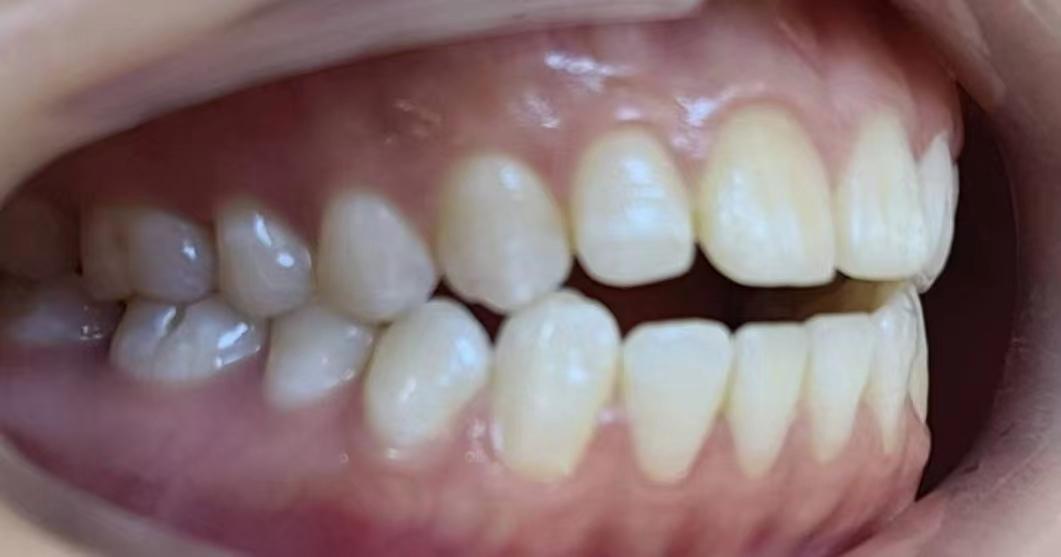

平時(shí)我們看到的自己牙齒可能這樣

看起來好像也還行

但你從牙醫(yī)視角看過自己的牙嗎!

就這兩顆自由飛翔的大門牙~能不影響咱的顏值嗎